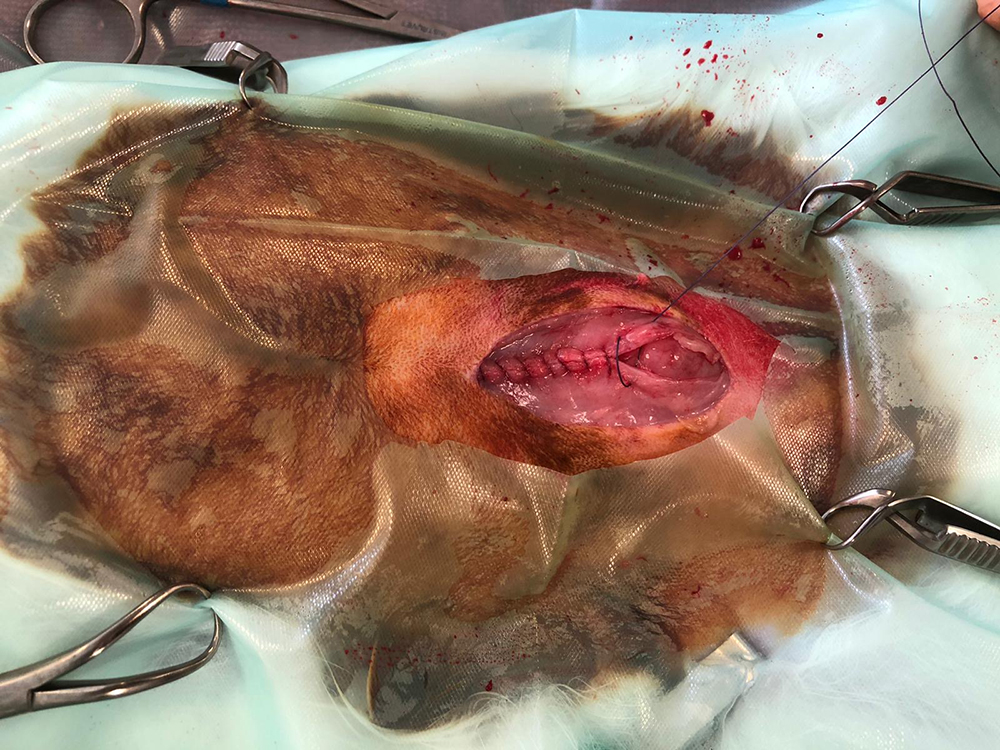

Nu kan de buik geopend worden, tot vlak voor het bekken. Om de buik open te houden, wordt de “lone star retractor” geplaatst. Hiermee is er goed zicht en werkruimte te verkrijgen. De eierstokken liggen bij het konijn vrij ver naar de zijkant, de darmen liggen vaak in de weg en zijn erg fragiel. Met de “lone star retractor” kan de sterilisatie veiliger worden uitgevoerd.

Na het afbinden van de bloedvaten worden de eierstokken en de baarmoeder verwijderd. Hierbij wordt goed opgelet dat ook daadwerkelijk de hele eierstok verwijderd wordt, wat soms lastig te zien is door het vet eromheen.

Hierna worden de buikwand, de onderhuid en de huid gesloten. Vaak is het weefsel heel dun waardoor het hechten lastig kan zijn. Het is zaak om de hechtingen goed onder de huid te krijgen.

Hieronder de sterilisatie van het konijn in beeld